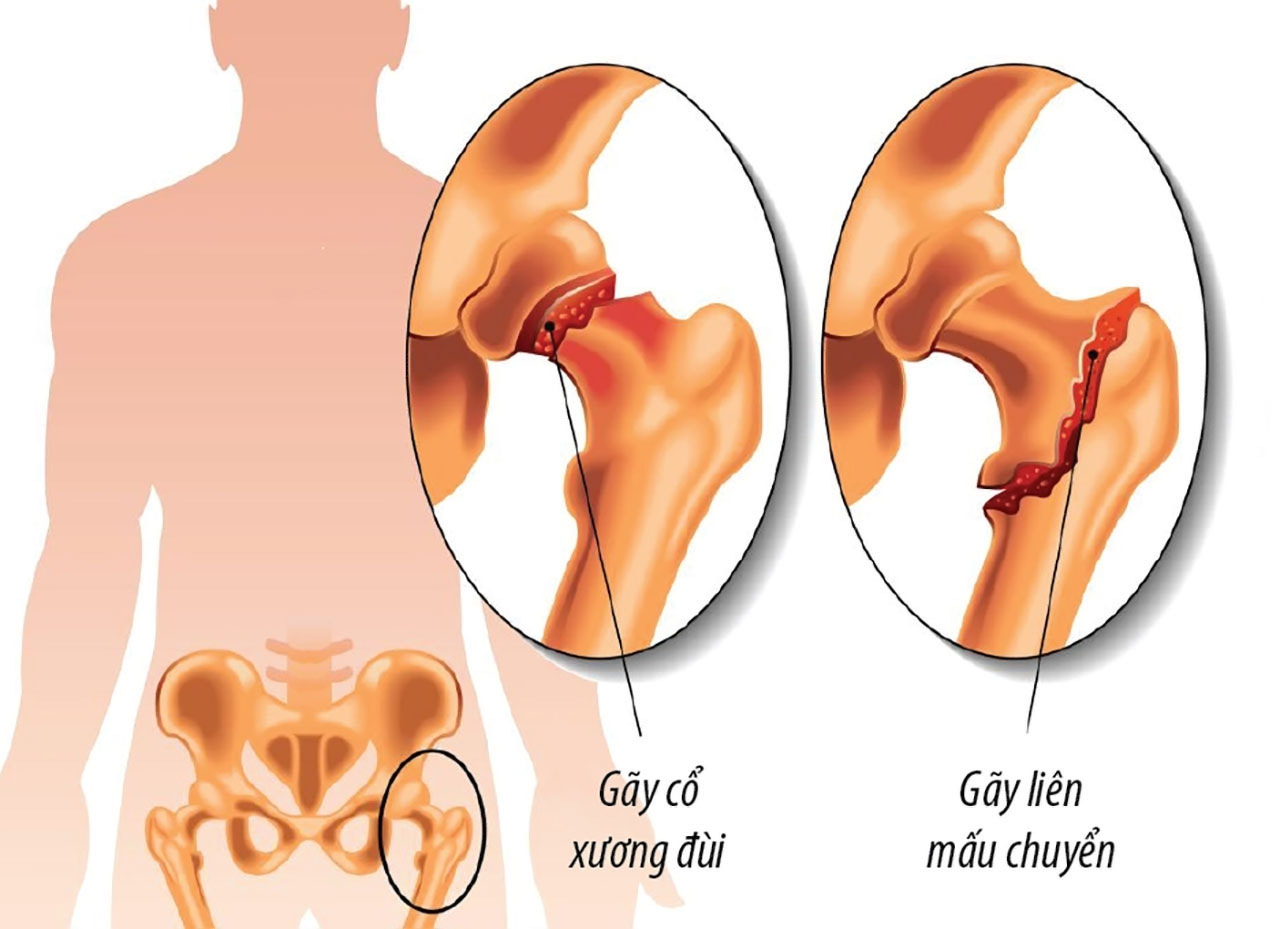

Dấu hiệu gãy cổ xương đùi

Sau chấn thương hoặc té ngã thấy các dấu hiệu như sau:

- Thấy đau vùng háng, đau tăng khi ấn vào nếp gấp bẹn hay có lực dồn ép từ gót chân.

- Mất vận động một phần hay mất hoàn toàn vận động khớp háng.

- Chẩn đoán xác định bằng chụp phim xquang khung chậu và khớp háng bên nghi ngờ gãy cổ xương đùi.